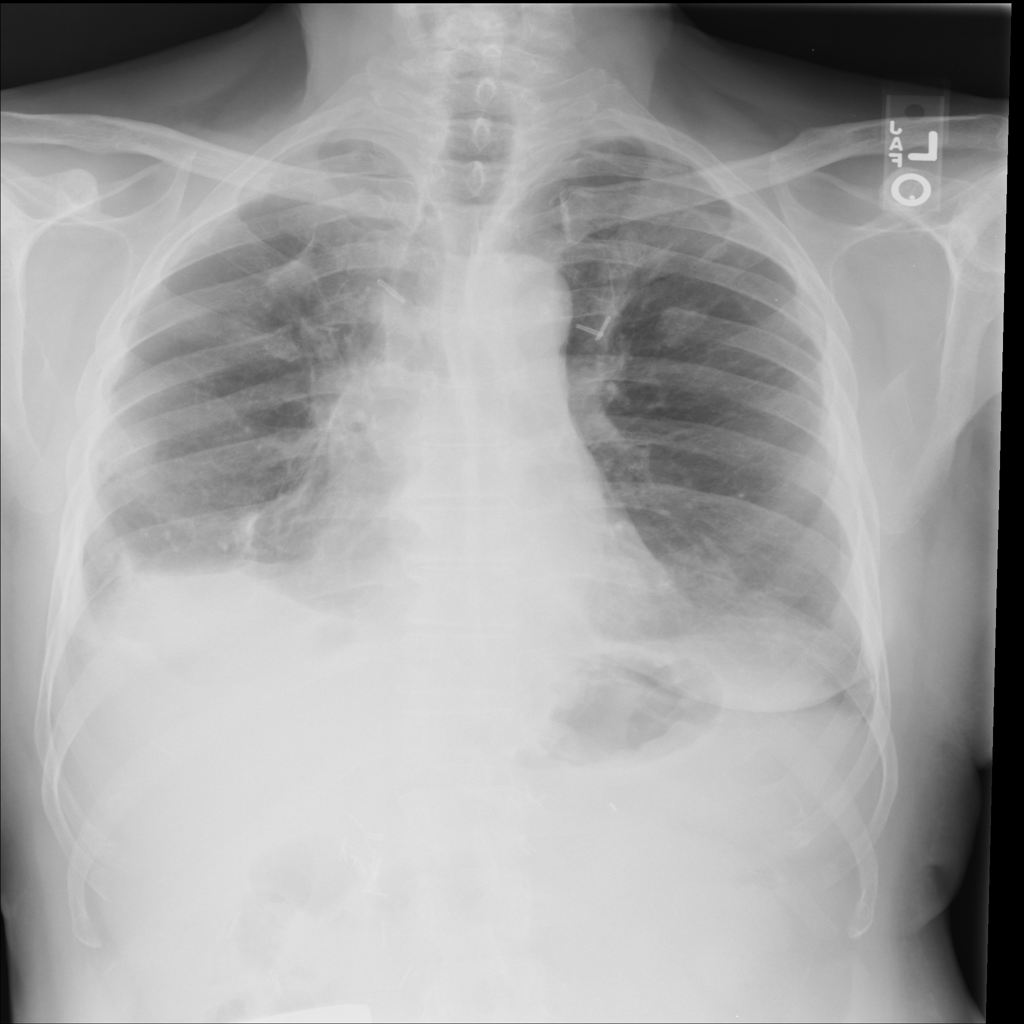

Nodule

A nodule is a small rounded opacity in the lung or chest field. It is a descriptive imaging finding that can be benign or more concerning depending on size, appearance, and context.

Showing up to 90 reference images for Nodule.

PAT-250B · IMG-000Nodule

PAT-250B · IMG-000

PA